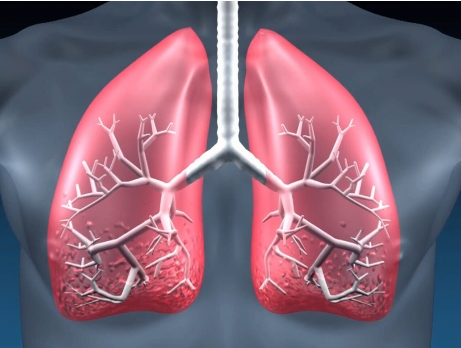

特发性肺纤维化(IPF)是一种不明原因的慢性进行性致纤维化性间质性肺炎,通常出现于成人,局限于肺部。肺纤维化预后比较差,目前针对肺纤维的特效药主要有尼达尼布(乙磺酸尼达尼布软胶囊)和吡非尼酮,可以有效控制肺纤维化进展,延长无进展生存期,提高患者生存质量。